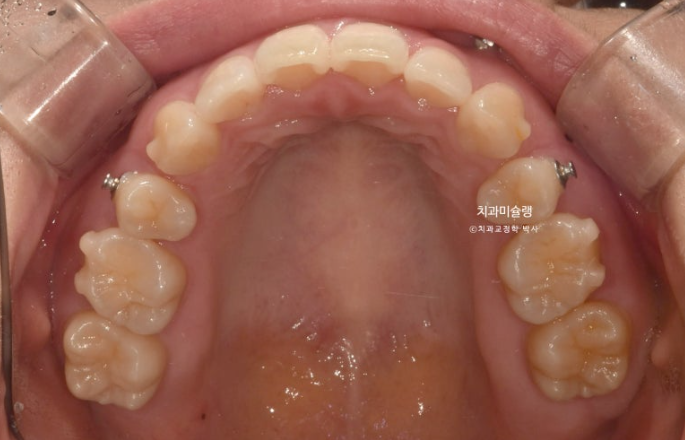

중심선은 잘 맞으며 과개교합을 개선하기 위한 교정용 나사를 심고 진행했습니다.

상악 발치공간이 양측으로 각각 1mm씩 남은 상태라서 재제작에 들어갔습니다.

발치공간이 소량 남은 것 이외에 치아 뿌리 평행도도 양호하고 어금니 쓰러짐도 없이 잘 진행된 편이라 이때까지만 해도 토탈 치료기간이 토탈 2년을 넘지 않을 것으로 예상했습니다.